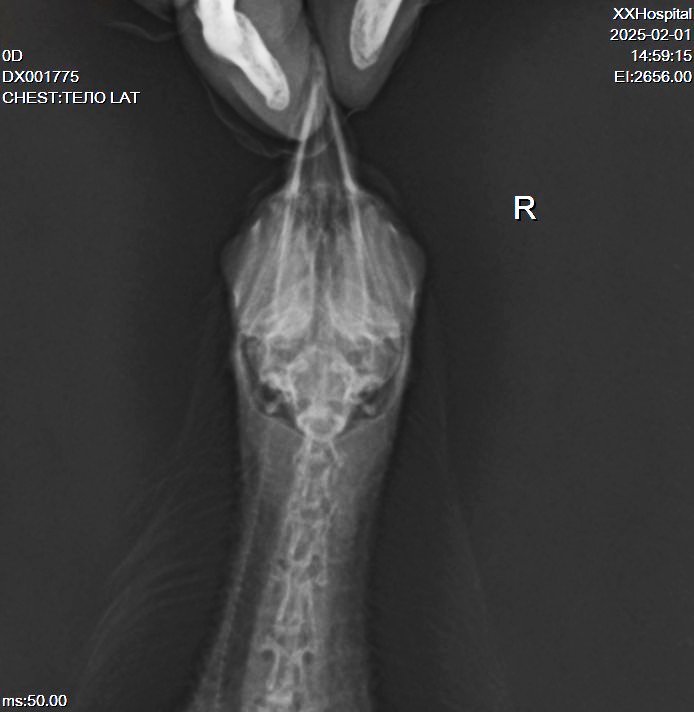

рентен нужно в двух проекциях сверху и сбоку и позвоночник и ноги и крыло

Добрый день! Были на рентгене. Травм не обнаружили. Есть застойные явления в легких, возможно, из-за отсутствия движения. Рентгенолог сказала, судя по симптомам, нельзя исключать менингит.

Вечер добрый! Мы наконец повторили рентген. @Zosia не могли бы взглянуть, пожалуйста?

DX001775_3.jpg

На снимке странно выглядит зона,где должен находиться коракоид. Возможно имеем его перелом. Если это так- то понятно отсутствие возможности летать и общая вялость,т.к. это чрезвычайно болезненный перелом и опасный...

Почему на правом крыле вы видите "шишку"- непонятно. Внешне сустав (локтевой) правого крыла без изменений.

Вообще все положение тела птицы несколько "скособочено" вправо... возможно был плоский удар (машина), и имеются отечные явления

Череп на ВД снимке без патологий.

На лат проекции есть некие объекты, в зоне гонад/яичника, больше похожие на гранулемы яичника .

Пока кроме продолжения терапии НПВС, миорелаксантами, витаминами В6 и В12, источниками кальция- нечего добавить (по части преджполагаемой травмы).

@Zosia Огромное спасибо!!! Какаем нормально, с этим проблем нет! Шишка у на здесь (отметила кружочком)

Он "бережет" правую лапу, если наступает, то на кулачек. Или держит на весу. На правой стоит нормально. Правое крыло тоже не рабочее. Иногда, если перенервничает, закидывает голову назад, вплоть до кувырков на спину. В спокойном состоянии голову держит ровно. Энтерофурил не пили. Приняла к сведению!